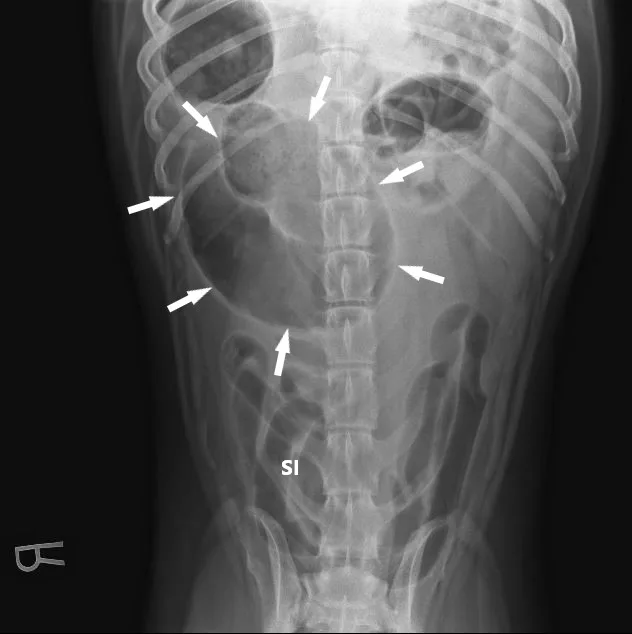

A lubricated 10 French red rubber catheter was inserted rectally and connected to a 60-mL catheter-tip syringe. Air (2 mL/kg) was injected while the anus was occluded by pinching off the anal tissue. Additional 3-view abdominal radiographs revealed normal-diameter, gas-filled small intestines; a markedly gas-distended proximal colon; soft-tissue opacity abnormally located in the right cranial abdomen; and narrowing of the distal lumen of the descending colon (Figure 2). The remainder of the radiographs were unremarkable. Radiographs were assessed by multiple board-certified radiologists, and there was a high index of suspicion for colonic torsion.

Radiographic findings of colonic torsion include marked gas-filled colonic distention, abnormal location of the ascending or descending colon, and narrowing of the descending colon. The cecum may also be displaced.